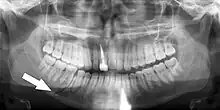

Panoramic radiograph showing Stafne defect (arrowed).

Dental panoramic radiograph showing dentigerous cyst (arrowed).